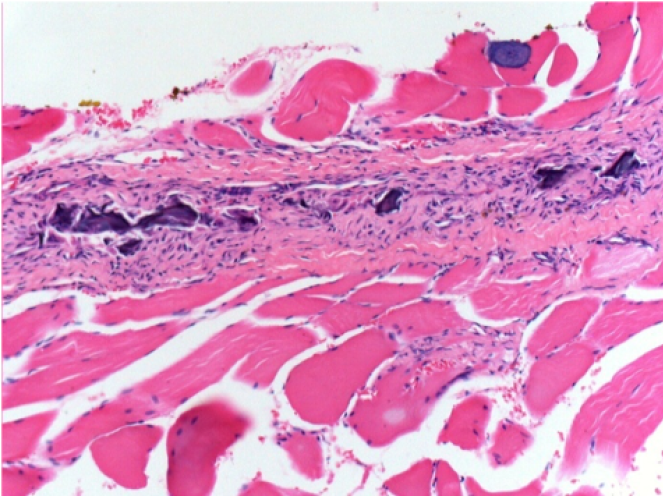

10 días después de la inyección de Endopeel

10 días después de la inyección de Endopeel 0,1 ml en el músculo pretibial derecho.

Aquí puede ver la formación de las vacuolas que están rodeadas de linfocitos. Las vacuolas son diferentes a la necrosis tisular. La presencia de linfocitos está relacionada con la permeabilidad de las membranas celulares.

L : Control-100xD10

R:100xD10

R :200xD10

R :400xD10